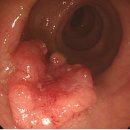

• 대장 | 영등포병원 건강검진 대장내시경 후기 30살에 용종제거⁉️

​ 영등포병원 대장내시경 후기 30살에 용종제거⁉️ 영등포병원 ⏰월-금 08:30-17:30 토요일 08:30-12:30 일요일 정기휴 ☎️ 02-2632-0013 영등포병원 서울특별시 영등포구 당산로31길 10 영등포병원 안녕하세요 30살에 대장내시경하고 용종 뗀 사람의 대장내시경 후기입니다 식단 저는 서울 영등포병원 건강검진 센터에서...

• 대장 | 녹십자 아이메드 강남 건강검진 위/대장 내시경 후기

으로 건강검진을 받고 왔습니다 위, 대장 내시경 포함해서 받고 왔는데 저번엔 다른 병원 건강검진받았었는데 여기도 괜찮더라고요 ​ 대장 내시경 준비~건강검진 후기 시작해 볼게요! ​ 대장 내시경 준비 검진 12시간 전~ Previous image Next image 대장 내시경을 받으시는 분들은 1주일 전 택배가 옵니다 ​ 저는 오전 7시...

• 대장 | 부천 위대장내시경 후기 대장내시경식사까지

부천 건강검진 위대장내시경 후기 장좋은내과 건강검진 받는김에 ​ 별도로 검사 비용 지불하고 위랑 대장 내시경검사도 함께 받았습니다 (위대장내시경 비용 궁금하신 분들은 댓글)​ ​ 병원은 부천 상동 세이브존 6층에 위치한 장좋은내과로 방문했습니다 ​ 긍정적인 후기가 많았고 통화로 이것저것 여쭤봤을 때 다른 병원들...

• 대장 | 상남자의 일상: 대장내시경 후기

내시경을 할 때 약물 따위에 의존해서는 안되는 법이다. ​ ​ 하지만 일반 내시경을 의연하게 받아 들이던 상남자 게츠비에게도 두려움의 대상이 있었다. 바로 대장 내시경이다. 입구가 아닌 출구로 관입해야 하는 두려움(의사 선생님한테 위내시경 하면서 그냥 더 깊숙하게 넣어서 대장까지 검사하면 안 되냐고 물어봤는데...

• 대장 | 이샘병원 수면내시경 및 종합 건강 검진 후기 대장내시경 식사 식단 꿀팁

반갑더라구요😄😄 하지만.. 둘 다 물을 못 마시고 배가 고파서 힘이 없었어요! 빨리 끝나고 물 마시고 싶다는 생각밖에 없었습니다ㅎ ​ ​ 그리고 대망의 수면 위, 대장 내시경을 위해 바늘을 꽂는데 살짝 따끔했어요.. 덩치는 산 만하지만 바늘을 싫어합니다..ㅎ 맨날 와이프가 놀려요 수면 내시경 후기​ 이동형 침대에 옆...